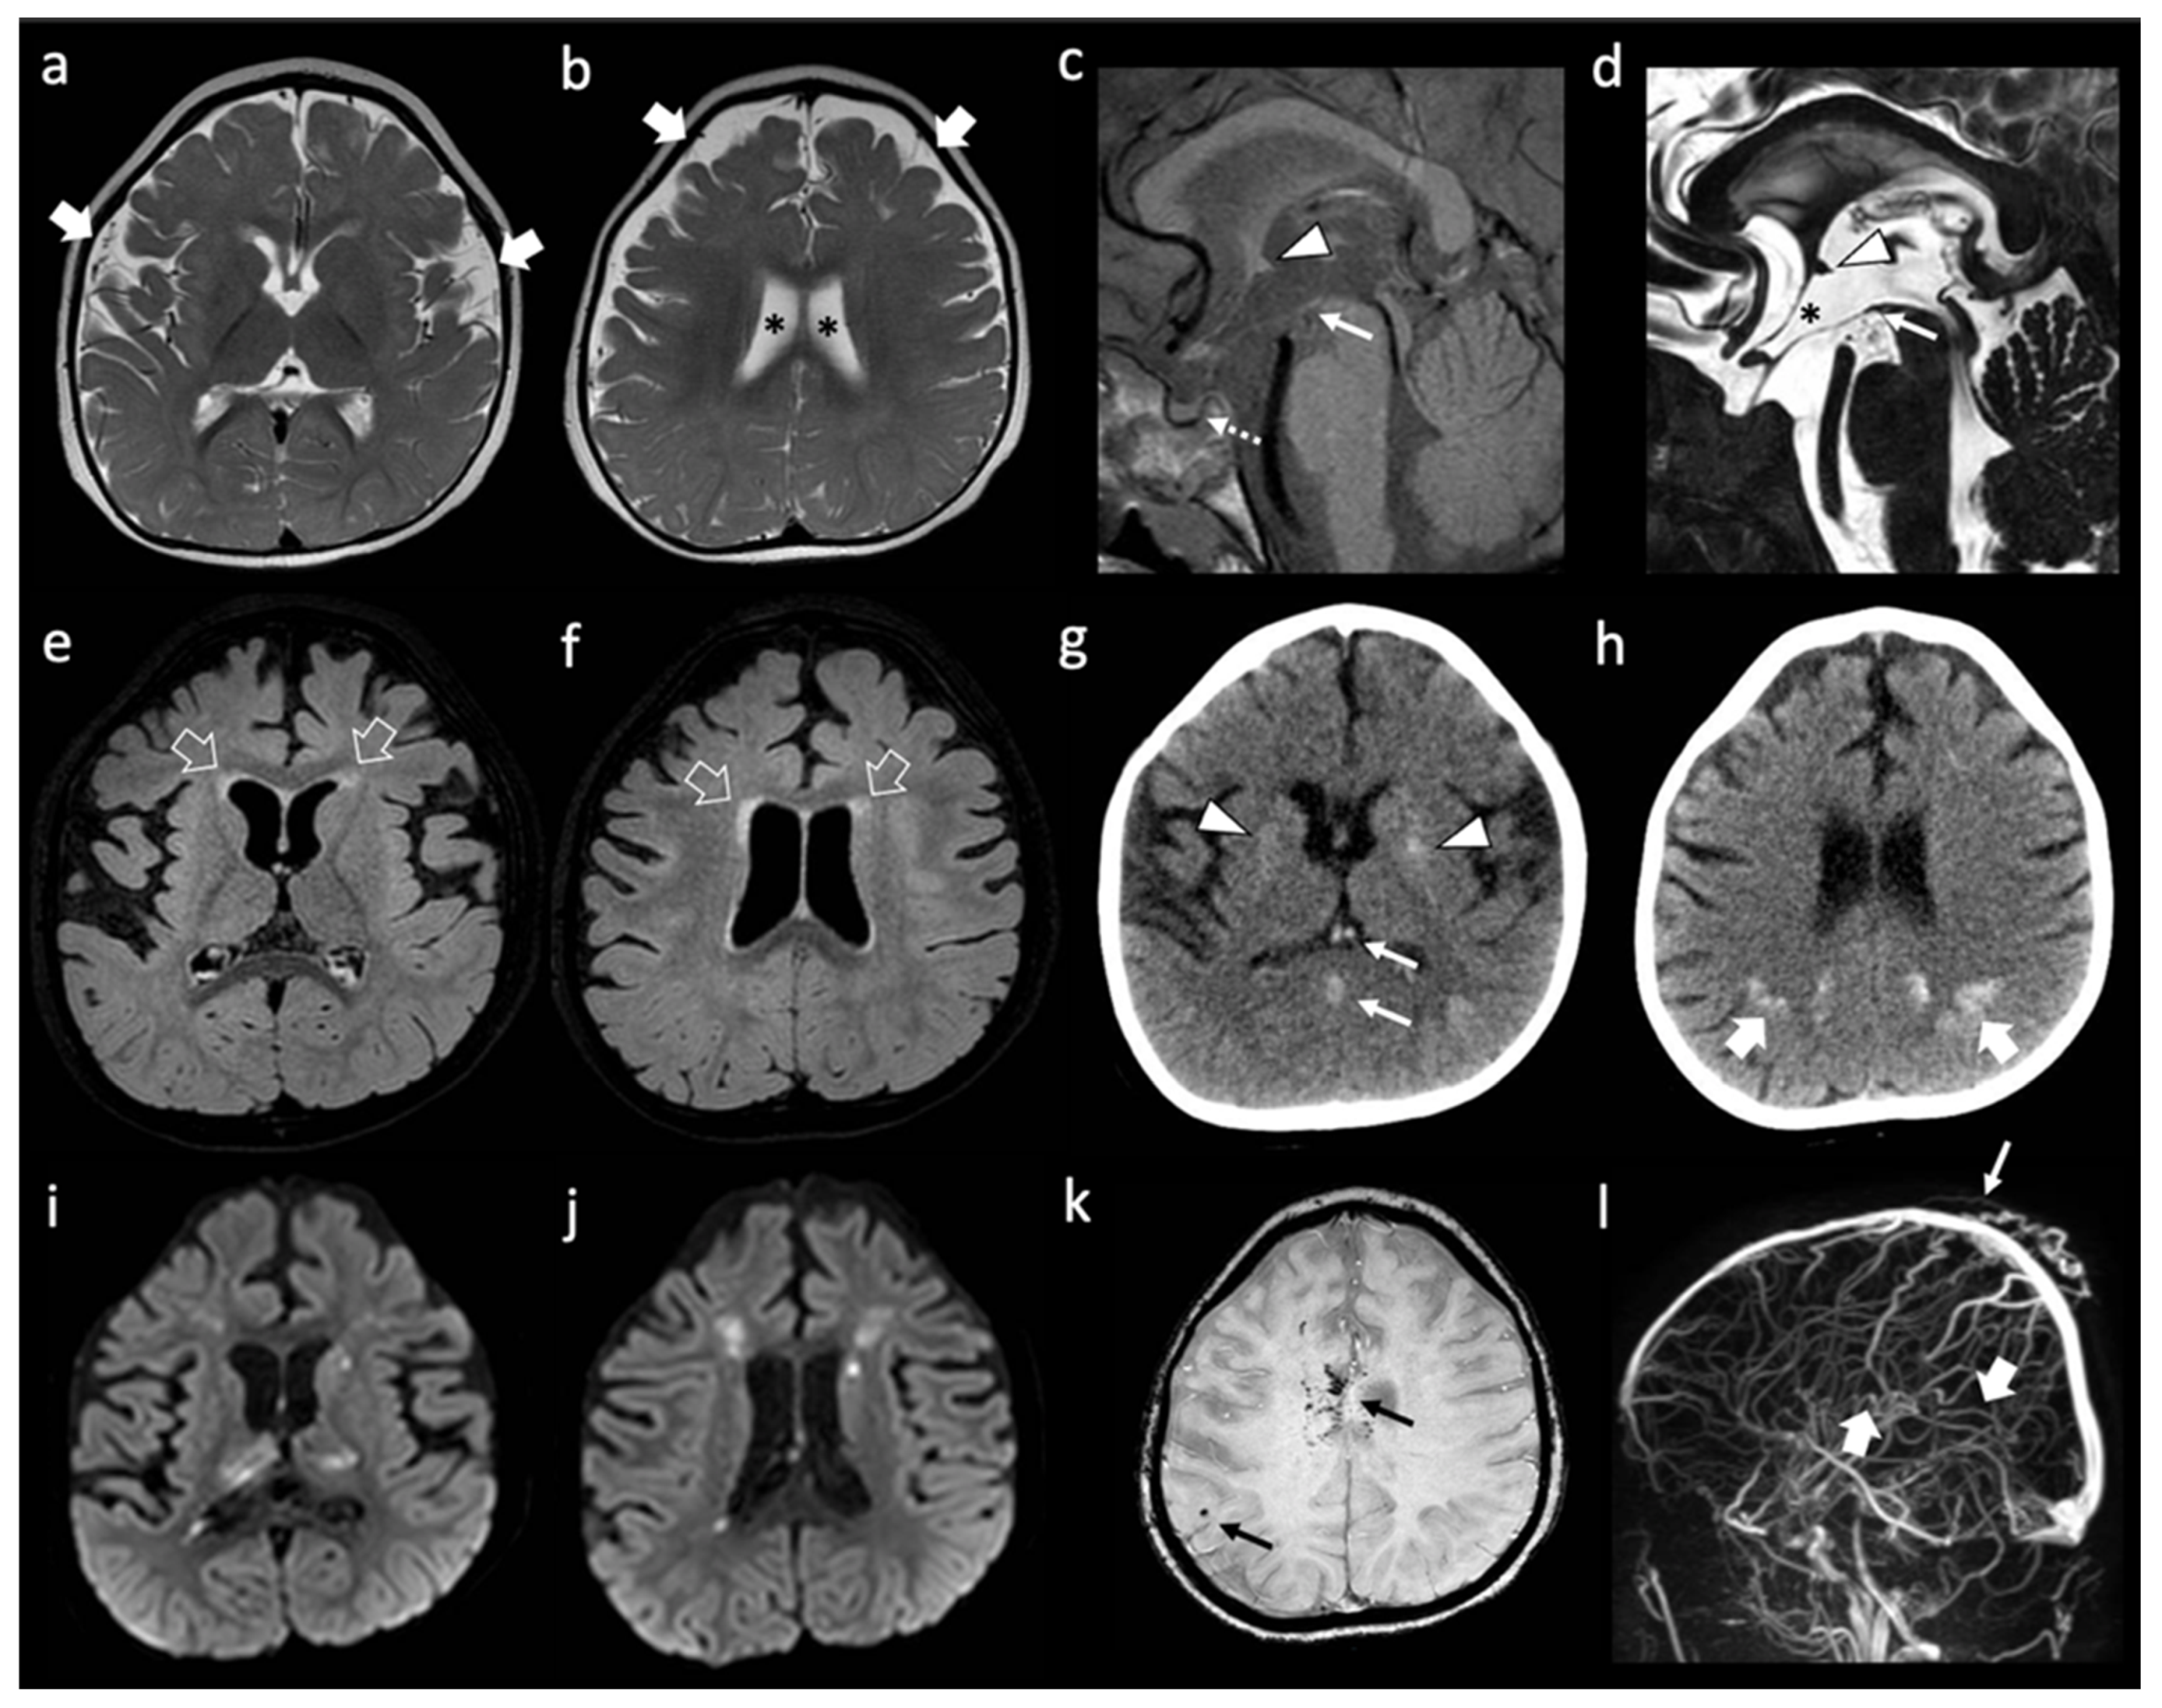

She is a Caucasian girl who came to our attention at the age of 2 years and 7 months for clinical suspicion of Rapid-onset Obesity with Hypothalamic Dysfunction, Hypoventilation, and Autonomic Dysregulation (ROHHAD) Syndrome [37]. She presented with a severe psychomotor delay, no autonomous de-ambulation, language deficit, axial hypotonia, worsening obesity, episodic fevers in the absence of infection (sterile pyrexias) (T = 39 °C), sleep disorder, constipation, onychodystrophy, and acanthosis nigricans. No other systemic manifestations were present. Blood tests confirmed hypothyroidism, hypo-adrenalism, hypernatremia, hyperchylomicronemia, hypertriglyceridemia, hypercholesterolemia, and diabetes insipidus. Dysmorphic features included plagiocephaly, protruding occipital lumps, thin eyebrows, long pointed chin, and aquiline nose. Cardiological assessment, including ECG, was normal. Brain MRI performed at 1 year of age showed reduced white matter volume with enlargement of the frontal and temporal subarachnoid spaces and simplified gyral pattern (Figure 1a,b). In addition, absence of the posterior pituitary bright spot was noted. A follow-up brain MRI performed at 3 years of age revealed subtle signal alterations of the periventricular white matter in the frontal regions on T2/FLAIR weighted sequences, with stable enlargement of the subarachnoid spaces and lateral ventricles, associated with a parietal median sinus pericranii. Minor dysmorphisms of the third ventricle region were noted, including the abnormal shape of the anterior commissure, the thin, third-ventricle anterior recess, and small/dysmorphic mamillary bodies (Figure 1c–f). After four days, following an episode of dehydration due to acute gastroenteritis, sudden onset of mild right hemiparesis was noted by the parents, and a head CT and brain MRI were performed showing deep cerebral venous thrombosis involving sinus rectus, internal cerebral veins, anterior septal veins, the distal portion of the left basal vein of Rosenthal, and the choroid plexus draining veins (Figure 1g–l). Multiple venous ischemic lesions were evident in the thalami, left striatum, and in the anterior and posterior periventricular white matter (Figure 1i,j). Widespread subtle calcifications of the basal ganglia associated with marked band-like calcifications in the subcortical white matter of the left frontal and bilateral parietal regions were also evident (Figure 1g,h). Continuous intravenous unfractionated heparin (20 U/Kg/h) was administered, then shifted to subcutaneous low molecular weight heparin, and subsequently changed to warfarin. The patient’s family history was positive for cerebrovascular events in the maternal branch. Karyotype, array-CGH, and Sanger sequencing of PHOX2B, MECP2, and FOXG1 genes, as well as a Prader Willi Syndrome methylation test, were negative. Head CT of the father did not show silent cerebrovascular events nor pathological brain calcifications.

Figure 1.

Neuroimaging features of patient A. (a,b) Brain MRI with axial T2-weighted images performed at 1 year of life showing enlargement of the frontal and temporal subarachnoid spaces (thick white arrows) and of the lateral ventricles (black asterisks). Note, the simplified gyration of the cortex, especially in the fronto-temporal lobes. (c–f) brain MRI performed at 3 years of age with sagittal T1-weighted (c) sagittal DRIVE (d) and axial FLAIR (e,f) images reveal dysmorphic anterior commissure (white arrowheads), thin anterior recesses of the third ventricle (black asterisk), absent/dysmorphic mamillary bodies (white arrows), and absent posterior pituitary bright spot (dotted white arrow). There is mild FLAIR hyperintensity of the frontal periventricular white matter (empty white arrows). (g,h) non-enhanced head CT images performed a few hours after the onset of right hemiparesis, four days after the previous brain MRI, reveal spontaneous hyper-densities of the internal cerebral veins and straight sinus (thin white arrows). In addition, there are subtle, widespread calcifications of the basal ganglia (white arrowheads) and well-demarcated, band-like calcifications of the subcortical parietal white matter (thick white arrows). (i–l) A brain MRI performed the same day of the CT, including diffusion-weighted images (i,j) susceptibility weighted imaging (k) and phase contrast MR venography (l) confirm the absence of blood flow in the straight sinus and internal cerebral veins (thick white arrows) with associated multiple venous ischemic lesions in the thalami and periventricular white matter. In addition, small bleedings are observed in the fronto-mesial and right frontal subcortical white matter (thin black arrows). Note, the parietal median sinus pericranii (thin white arrow).